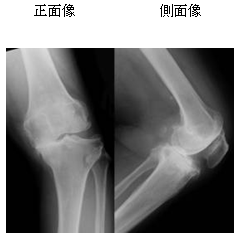

など、膝の痛みを患って病院に行って

レントゲンやMRIを撮っても骨に異常は見当たらず

血液検査も特に異常なし